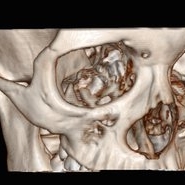

3D Image Of Intraocular Foreign Body

Sep 14 2014 by Mehul A Shah

14-year-old girl presented with penetrating injury to LE.

Photographer: Drashti Netralaya,Dahod

Imaging device: CT scan

Condition/keywords: intraocular foreign body